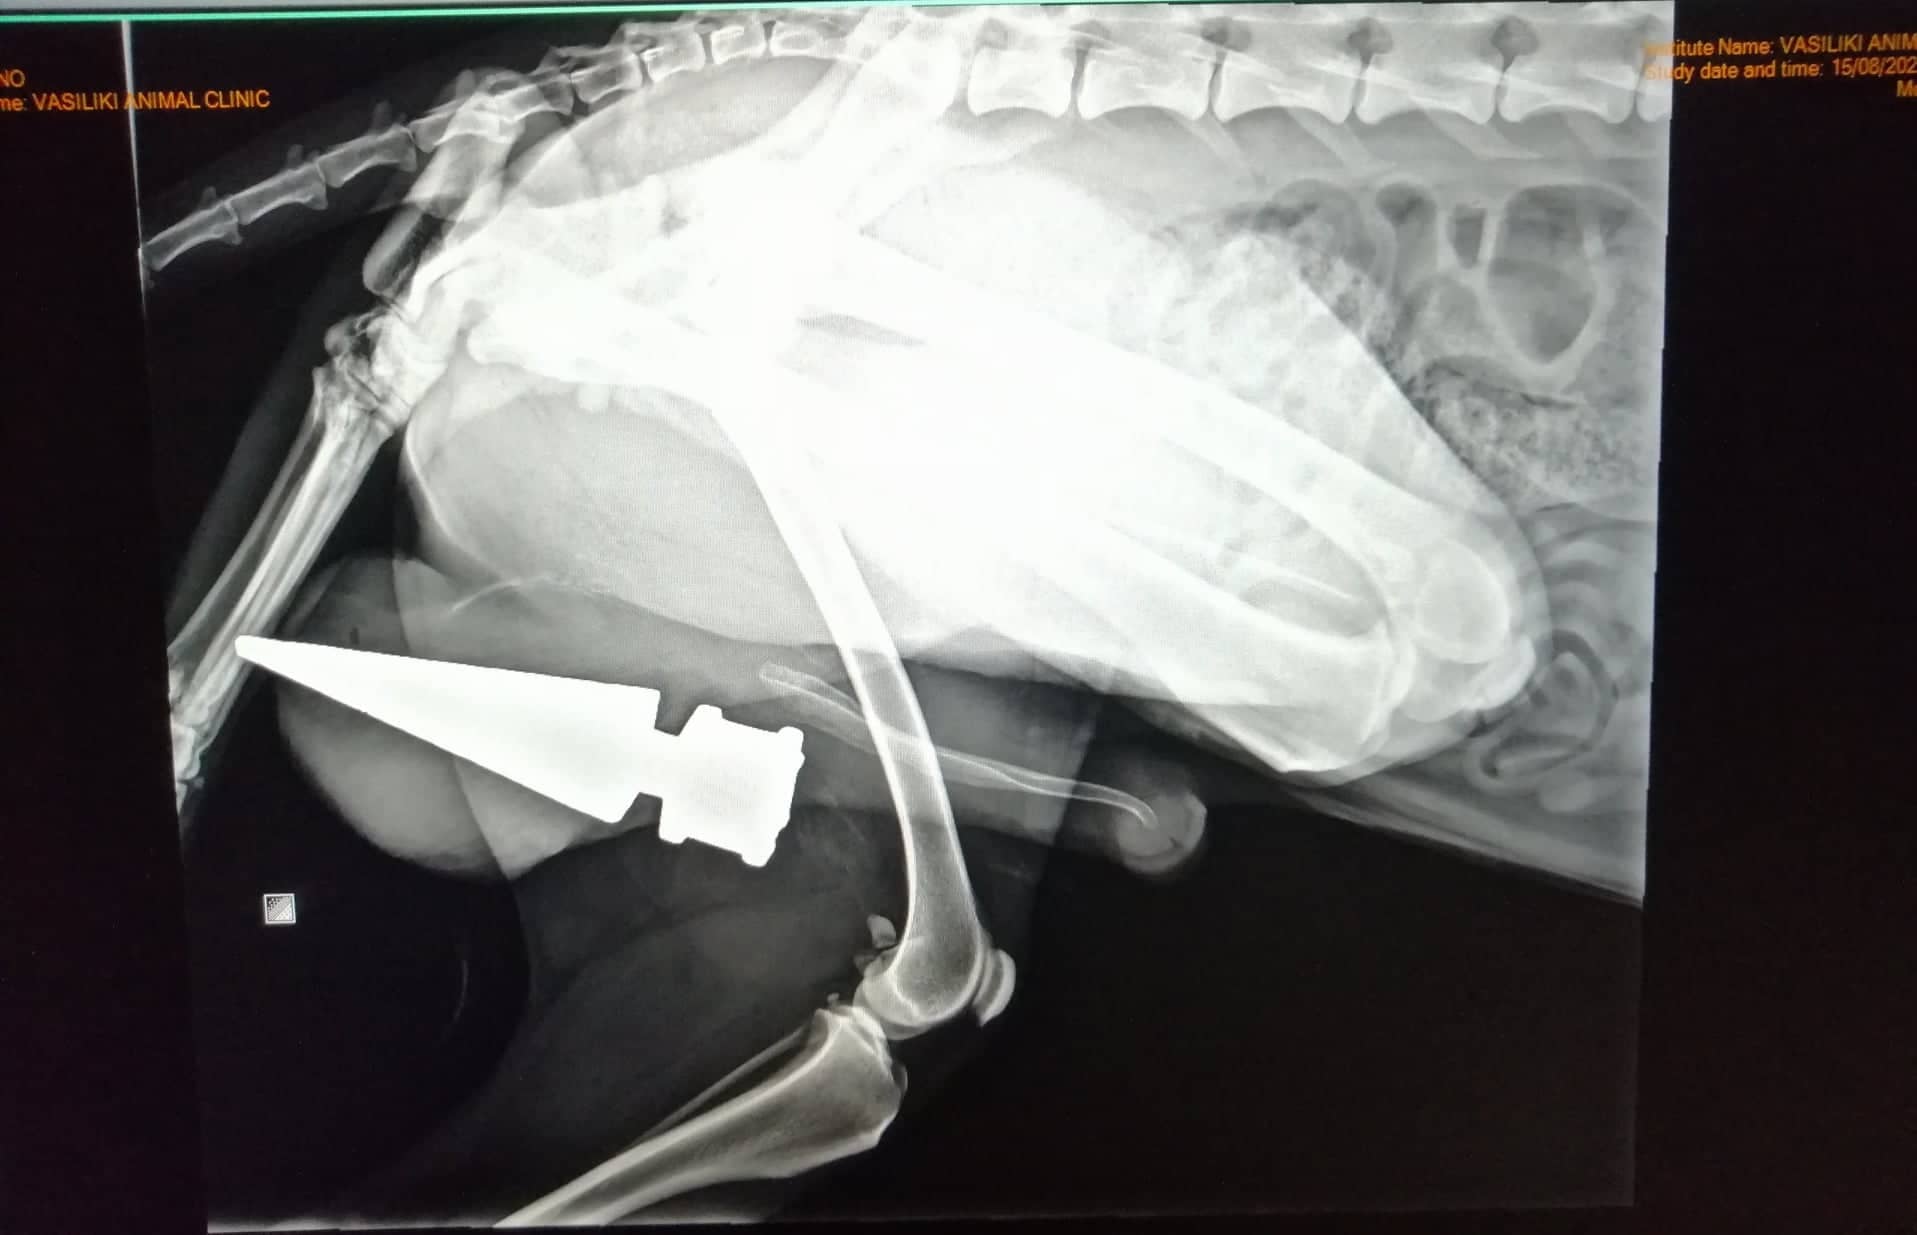

Αφού έγινε όλη η προετοιμασία με υπέρηχο, ακτινογραφία, ορούς και όλα τα σχετικά., κοιμίσαμε τον Μπρούνο με βοηθό? τον ίδιο τον μπαμπά του! ( το συνηθίζουμε τώρα τελευταία με τους συγγενείς των ασθενών μας ΧΑΧΑ).

Παρότι, ούτε κλινικά ούτε υπερηχοτομογραφικά είχα εντοπίσει κάποια αιμορραγία ( που ήταν το ελάχιστο αναμενόμενο), ο μεγαλύτερος φόβος μου ήταν η πιθανότητα το σιδερένιο αντικείμενο να είχε καρφωθεί σε κάποιο από τα μεγάλα αγγεία των όρχεων και να λειτουργούσε υπό την έννοια του επιπωματισμού ( να ταμπονάριζε δηλαδή το αγγείο και να μην άφηνε το αίμα να κυλήσει έξω από το σώμα του ζώου). Πολύ απλά, να είχε φράξει το αγγείο και γι'αυτό δεν έβλεπα το ζώο να αιμορραγεί.

Αν λοιπόν εγώ αφαιρούσα το καρφί βίαια, τότε θα είχα να αντιμετωπίσω μια ενδεχομένως θανατηφόρο αιμορραγία.

Το καρφί είχε περάσει ανάμεσα και πάνω από τους δύο όρχεις και είχε καρφωθεί μέσα στο όσχεο ( για να μιλήσουμε και λίγο επιστημονικά! μην μας λένε και δευτεράντζες!)

Και το καρφί το βγάλαμε, και αίμα δεν χάσαμε.........μόνο! Συγγνώμη Μπρούνο αλλά τους "όρχεις" τους χάσαμε! Δεν γινόταν αλλιώς!